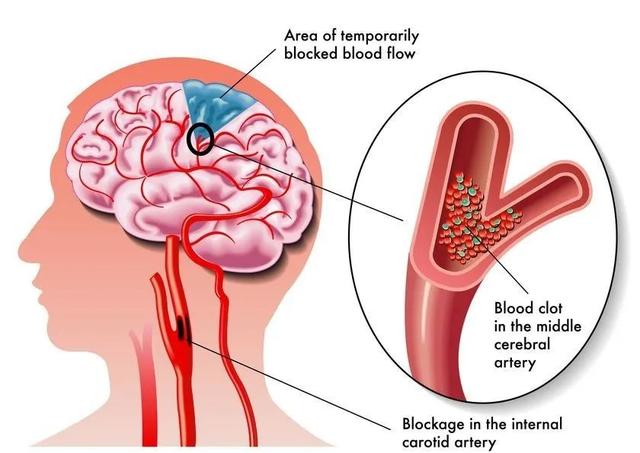

新冠病毒还会攻击神经系统,像病程中出现的嗅觉味觉丧失症状就是最好的证明。

Turner-Stokes医生解释道:“中国和意大利的数据显示,大约有三分之一的新冠患者在治愈后出现了神经系统损伤,从脑部炎症、神经损伤到谵妄、神经痛以及头痛都有出现。另外,它还会造成小血管损伤,影响器官供血。”

更严重的还会导致中风,纽约西奈山卫生系统神经外科医生Thomas Oxley就警告称:“就算是无症状或症状较轻的年轻患者也不能掉以轻心,新冠一样会造成中风。相比健康人群,患过新冠肺炎的人群的中风易感年龄段要年轻15岁。”